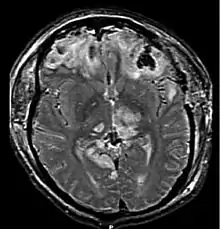

![]() Компьютерная томография, показывающая ушиб головного мозга | |